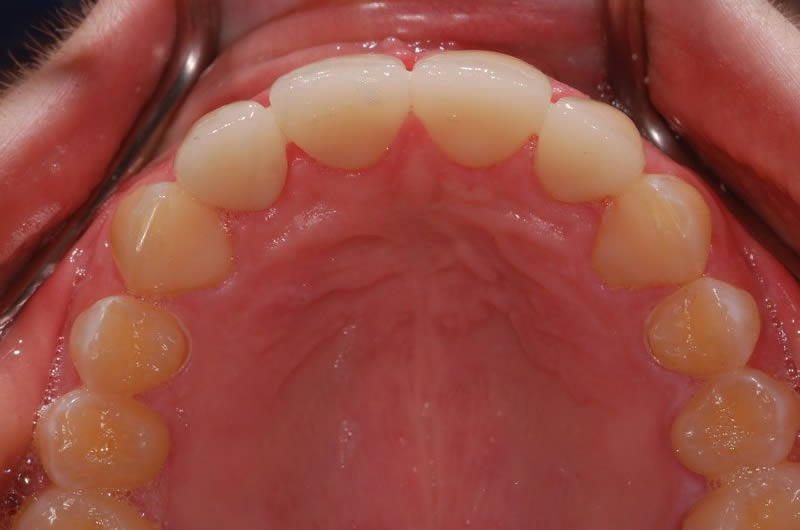

Case Studies

Dental Crowns (7 images)